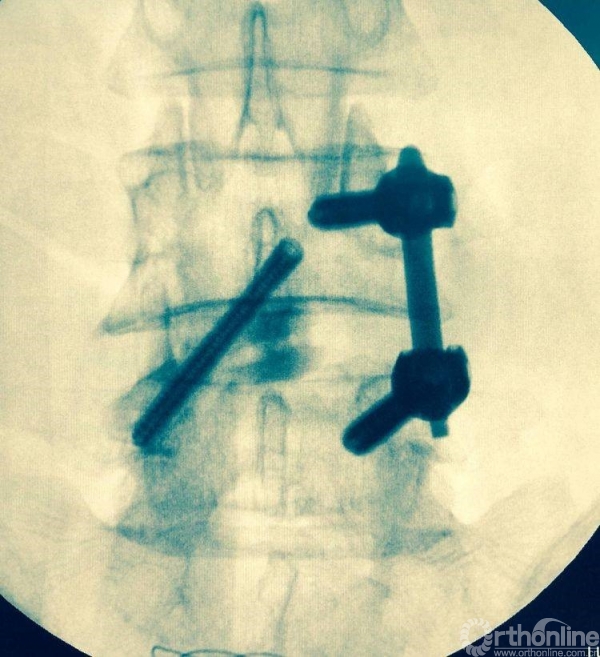

充分植骨(关节成型时的自体骨质、也可配合异体骨使用),然后植入融合器,镜下观察融合器和硬膜囊位置并透视再次确认

正侧位透视观察滑脱是否复位、融合器及植骨的位置

镜下观察有无碎骨块,融合器与硬膜囊位置关系

植入椎板钉、开路椎、扩展管、克氏针以及动力钻等应用

植入经皮椎弓根钉并加压